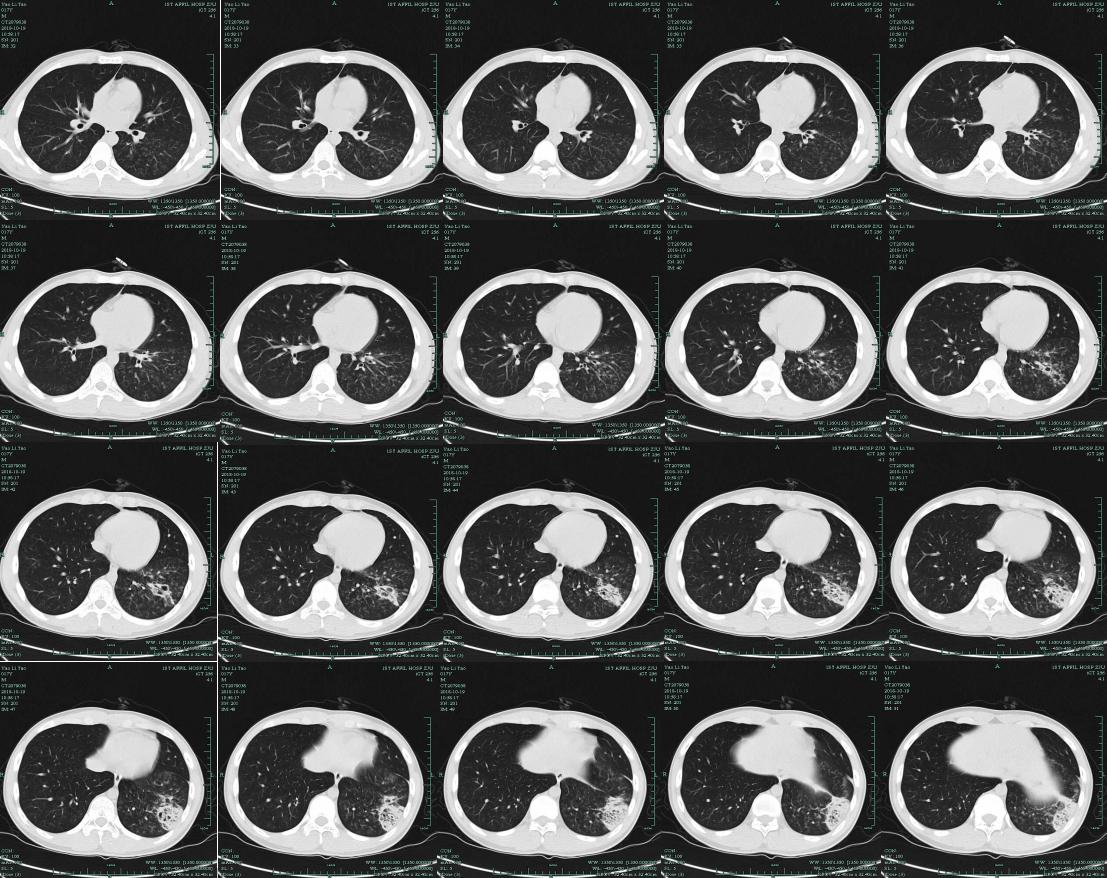

肺部CT(治疗后)提示双肺弥漫性病变,小叶性肺炎,左下肺斑片状阴影。

由于病人入院时病情严重,担心进行肺泡灌洗对他会有影响,所以进行了血mNGS检测……